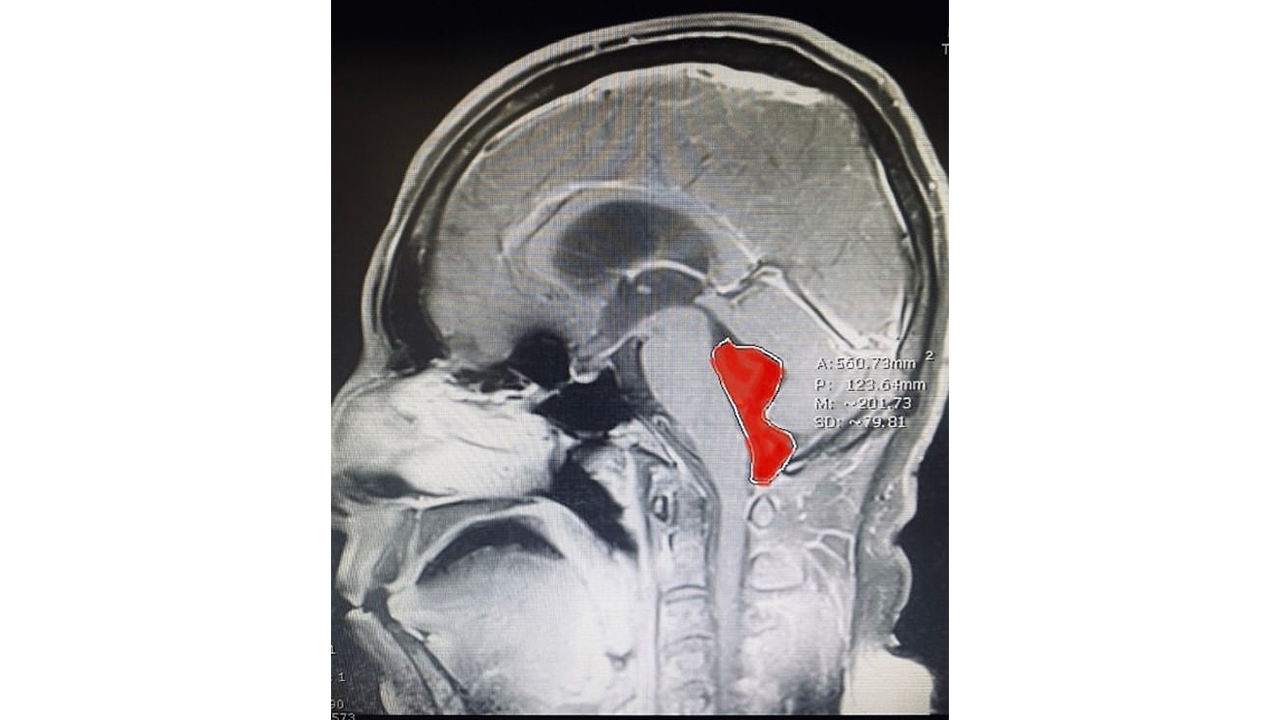

وعانى الرجل من آلام الرأس مدة طويلة جعلته يصاب بالغثيان في بعض الاحيان، وظن انه يعاني من ورم في الدماغ، وبعد الكشف الطبي وفحص الدماغ تبين وجود كتلة بالقرب من دماغه ظهرت باللون الأحمر وحجم حوالي 4 سم.